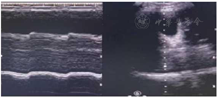

经后续20 d康复治疗:患者言语清晰,胸部CT双肺炎症明显吸收(图6),膈肌功能较前改善(图7)。拔出气切管。目前患者上、下肢关键肌肌力均达Ⅴ级。坐位平衡3级,可独立步行。ADL BI评分85分(进食10分、修饰5分、穿衣10分、控制大便10分、控制小便10分、如厕10分、床椅转移15分、平地行走15分)。